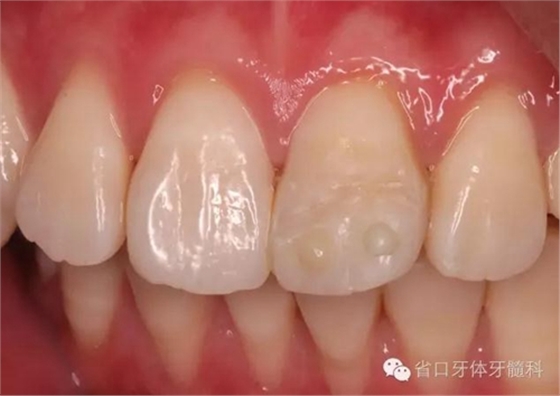

術前口內照

折斷之牙體嚴重脫水,呈白堊色,斷端對位后吻合度較好,僅少許牙體缺損。

口內照顯示口腔衛(wèi)生狀況不佳,21牙面呈亞光狀態(tài),齦緣輕度紅腫。

患者1個半月后復診,口腔衛(wèi)生狀況保持良好,牙齦健康,折斷線不可見。